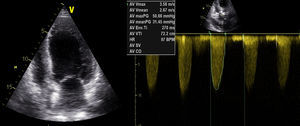

Atendendo ao quadro de instabilidade hemodinâmica com choque cardiogénico, foi decidida a realização de valvuloplastia aórtica (Figura 3) com balão NUCLEUS 20mm, sob ritmo de pacing a 220 bpm, verificando-se uma redução do gradiente de 97 para 46mmHg. Ao mesmo tempo, foi feita revascularização miocárdica completa com colocação de dois stents sem fármaco. A aortografia revelou insuficiência aórtica moderada, pelo que se optou pela não colocação de balão intra-aórtico.

O doente teve alta ao 24.° dia de internamento, em classe NYHA II. No ecocardiograma transtorácico à data de alta apresentava compromisso moderado a grave da FSG (Figura 4), gradiente valvular aórtico médio de 31mmHg e área valvular de 1,06cm2. Programou-se cirurgia cardíaca, após cumprimento de um mês de dupla antiagregação plaquetar.